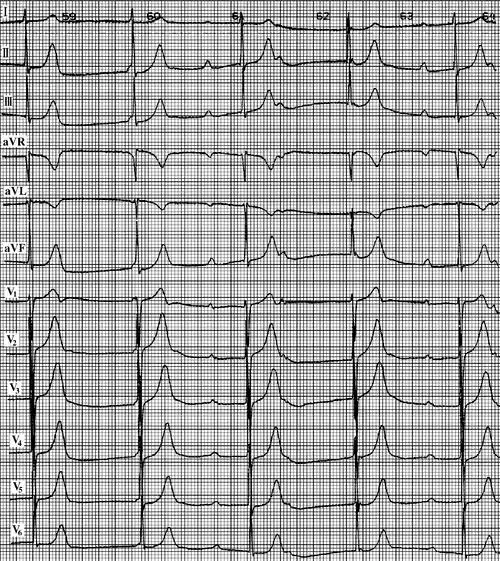

05s,为过缓的交界性逸搏心律,频率32/min.

这是交界性心律?逸博? - 心电图脑电图专业讨论版 - 爱爱医医学论坛

房室交界性逸搏和逸搏心律